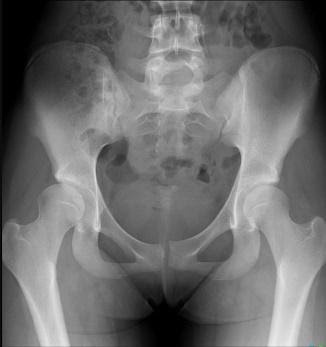

Children with moderate to severe dysplasia (4) may benefit from surgery such as a pelvic osteotomy to preserve the joint. Get an x-ray (figure 19)!

Figure 19